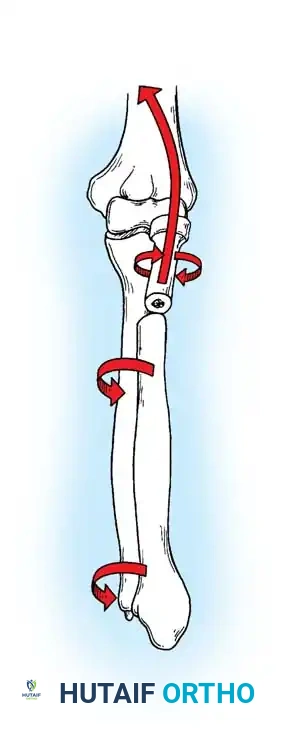

Biomechanics of the Tension Band:

The superficial (posterior) surface of the olecranon is the tension side of the bone. A figure-of-eight wire placed on this surface converts the tensile forces generated by the triceps into compressive forces across the articular fracture line, utilizing the humeral trochlea as a fulcrum.

Surgical Warning: A simple wire loop is biomechanically inferior to a figure-of-eight loop. If a simple loop is used—especially if its axis lies anterior to the mid-axis of the olecranon—the pull of the triceps will cause the fragments to separate posteriorly, leading to articular step-off and limited extension.

Fig. 54-53 A and B, Simple loop is not as satisfactory as figure-of-eight loop for fixing fracture of olecranon. C, Simple loop is insufficient when its long axis is in or anterior to long axis of olecranon.